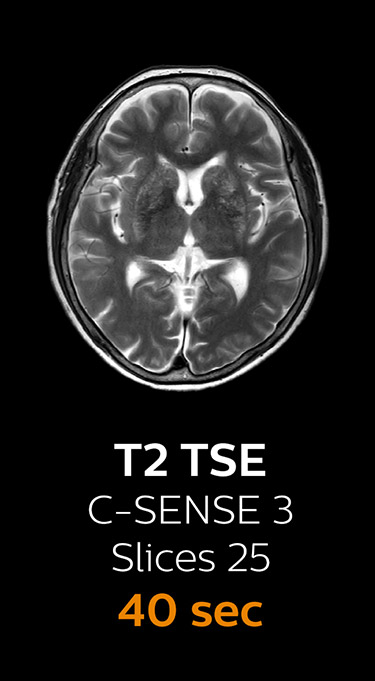

Scanning time reduction in brain MRI with Compressed SENSE

Fast MRI of brain

With Compressed SENSE, the scan time for the routine brain examination at KNC was reduced from 15:48 to 10:19 minutes, which corresponds to 35% reduction.

Ingenia 3.0T CX

Scan time 15:48 min.

Brain with Compressed SENSE

Ingenia 3.0T CX

Scan time 10:19 min.